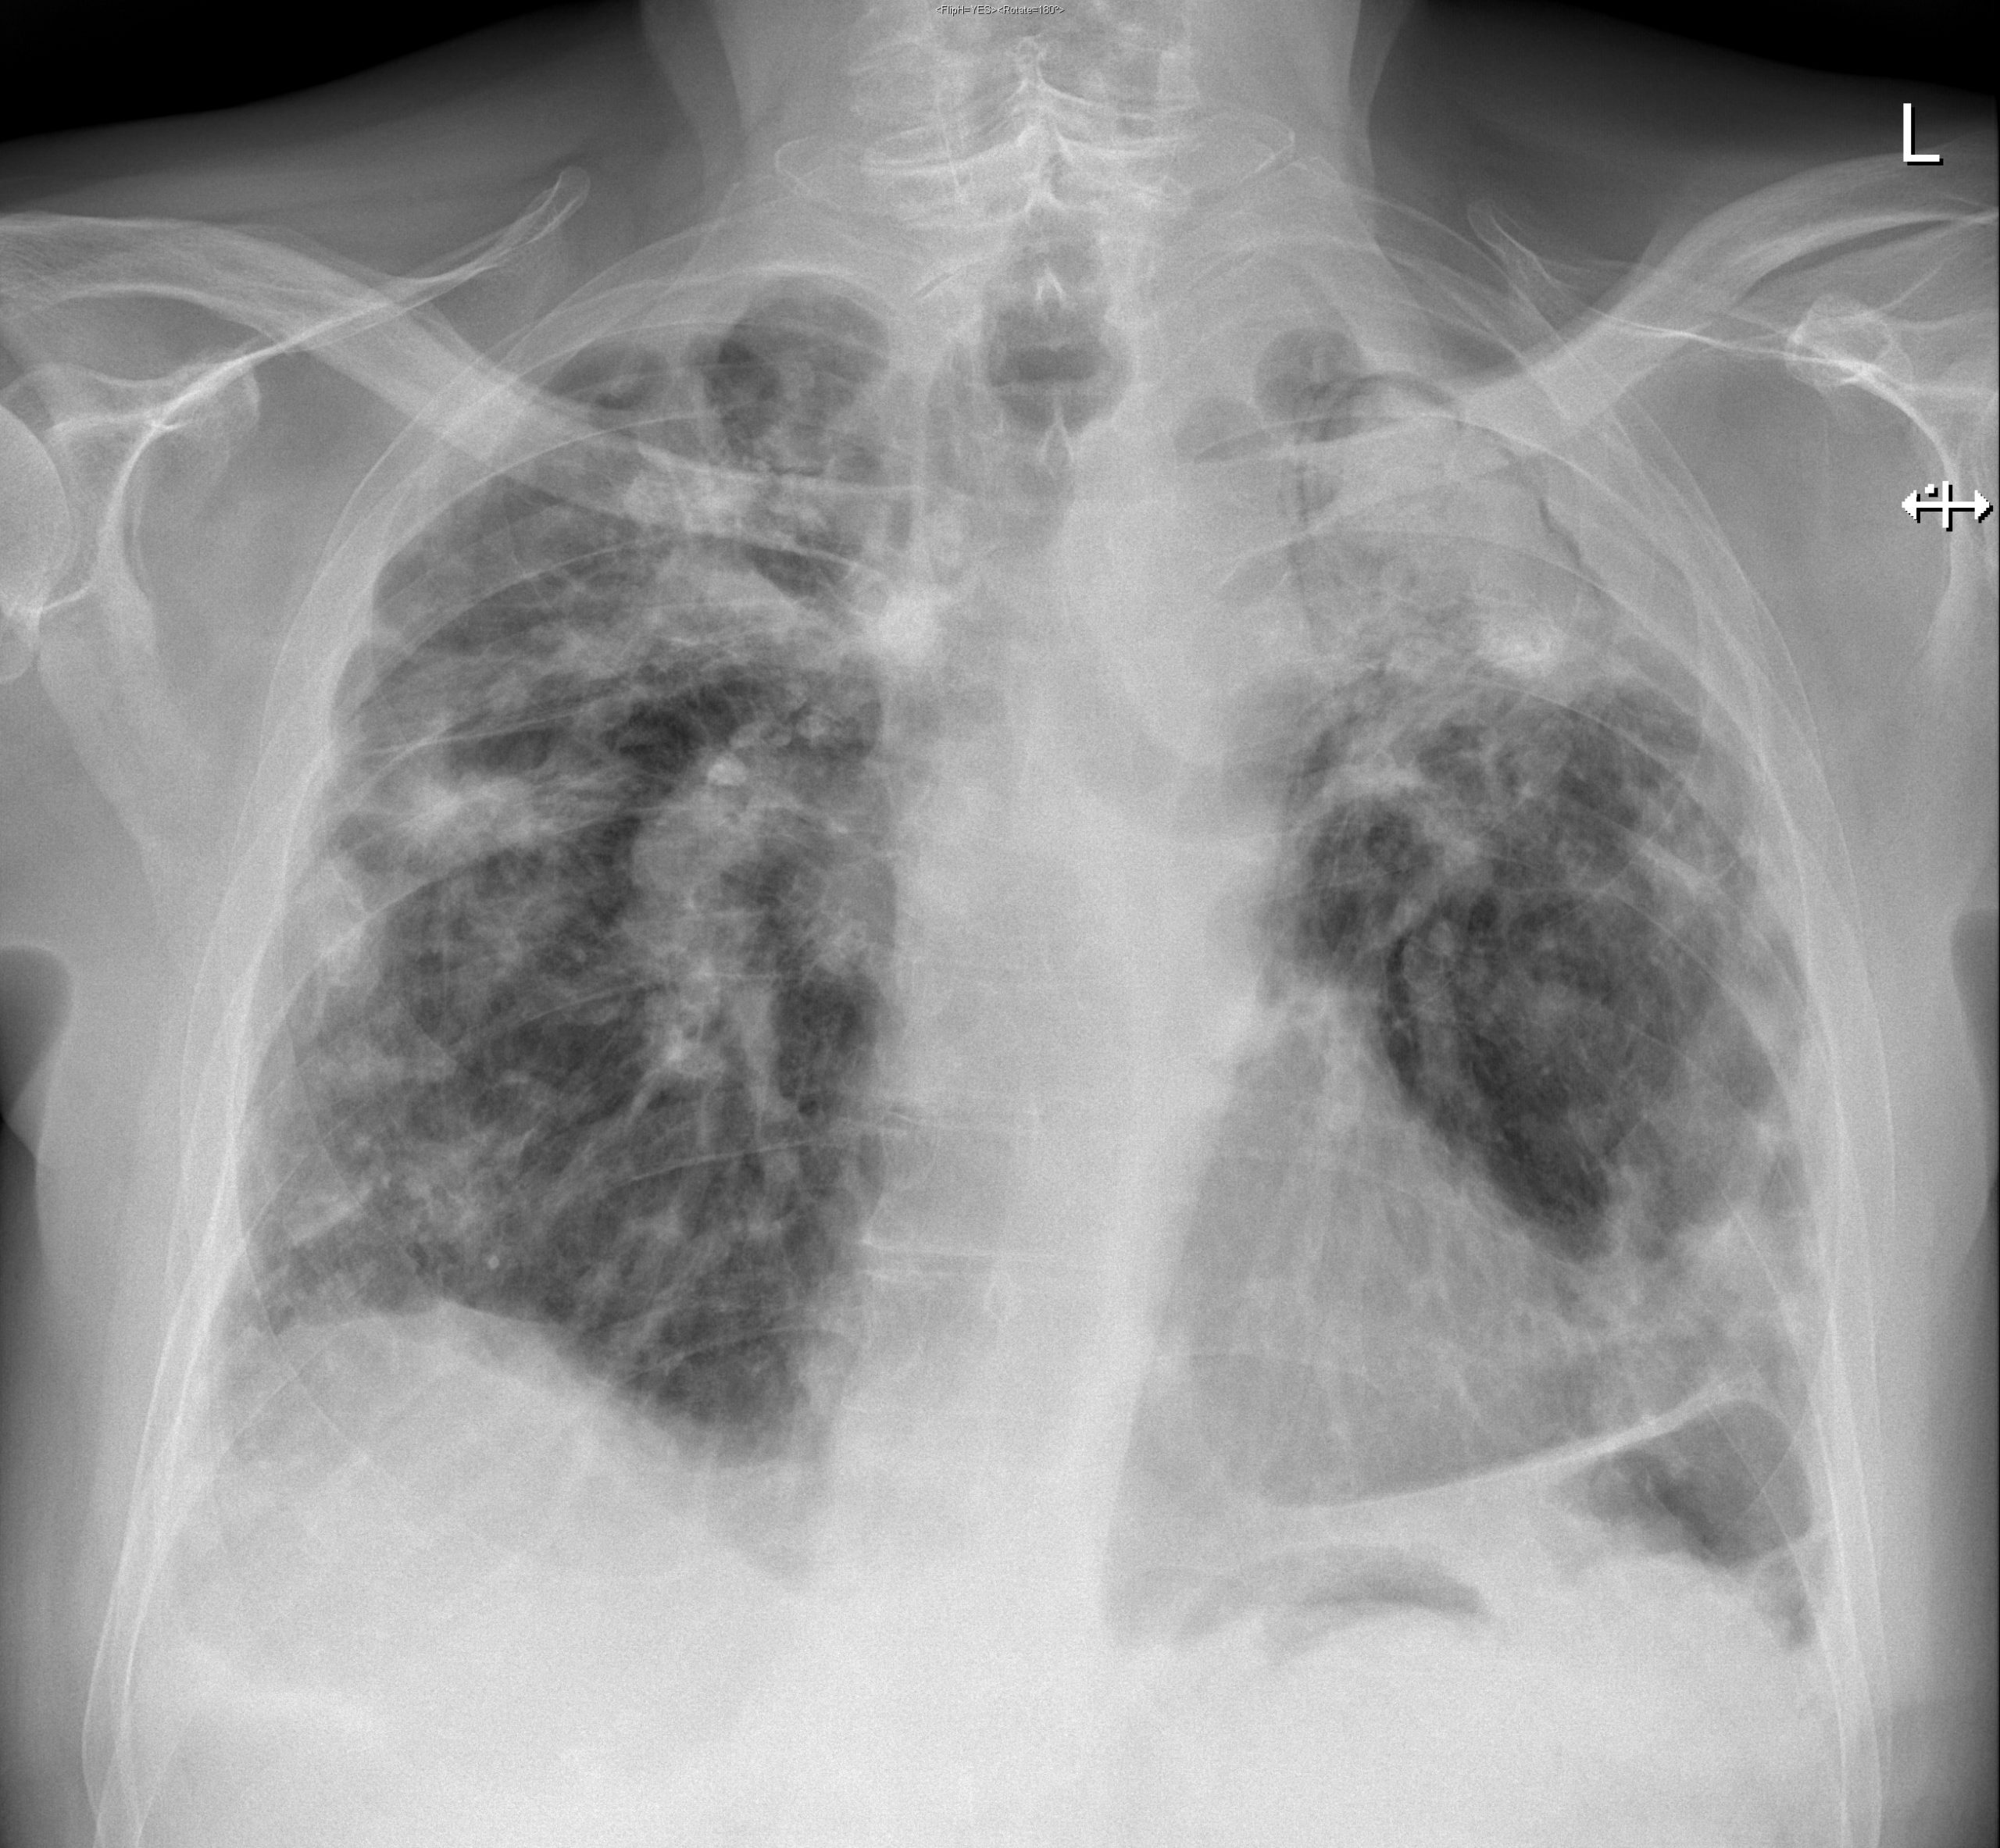

Визуализация и диагностика неинвазивного аспергиллеза с помощью КТ

Раздел: Необычные решения